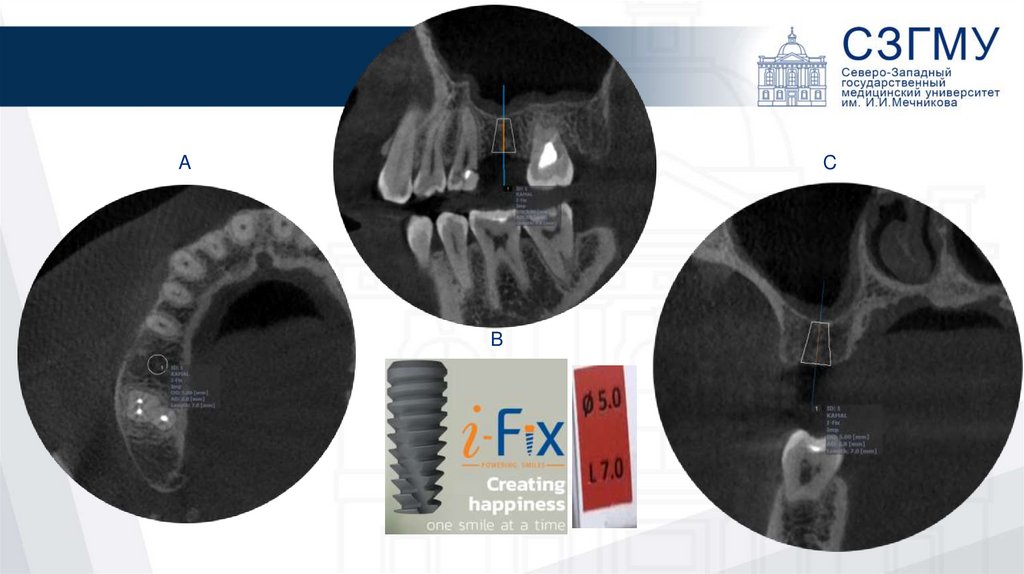

5.

A

C

B